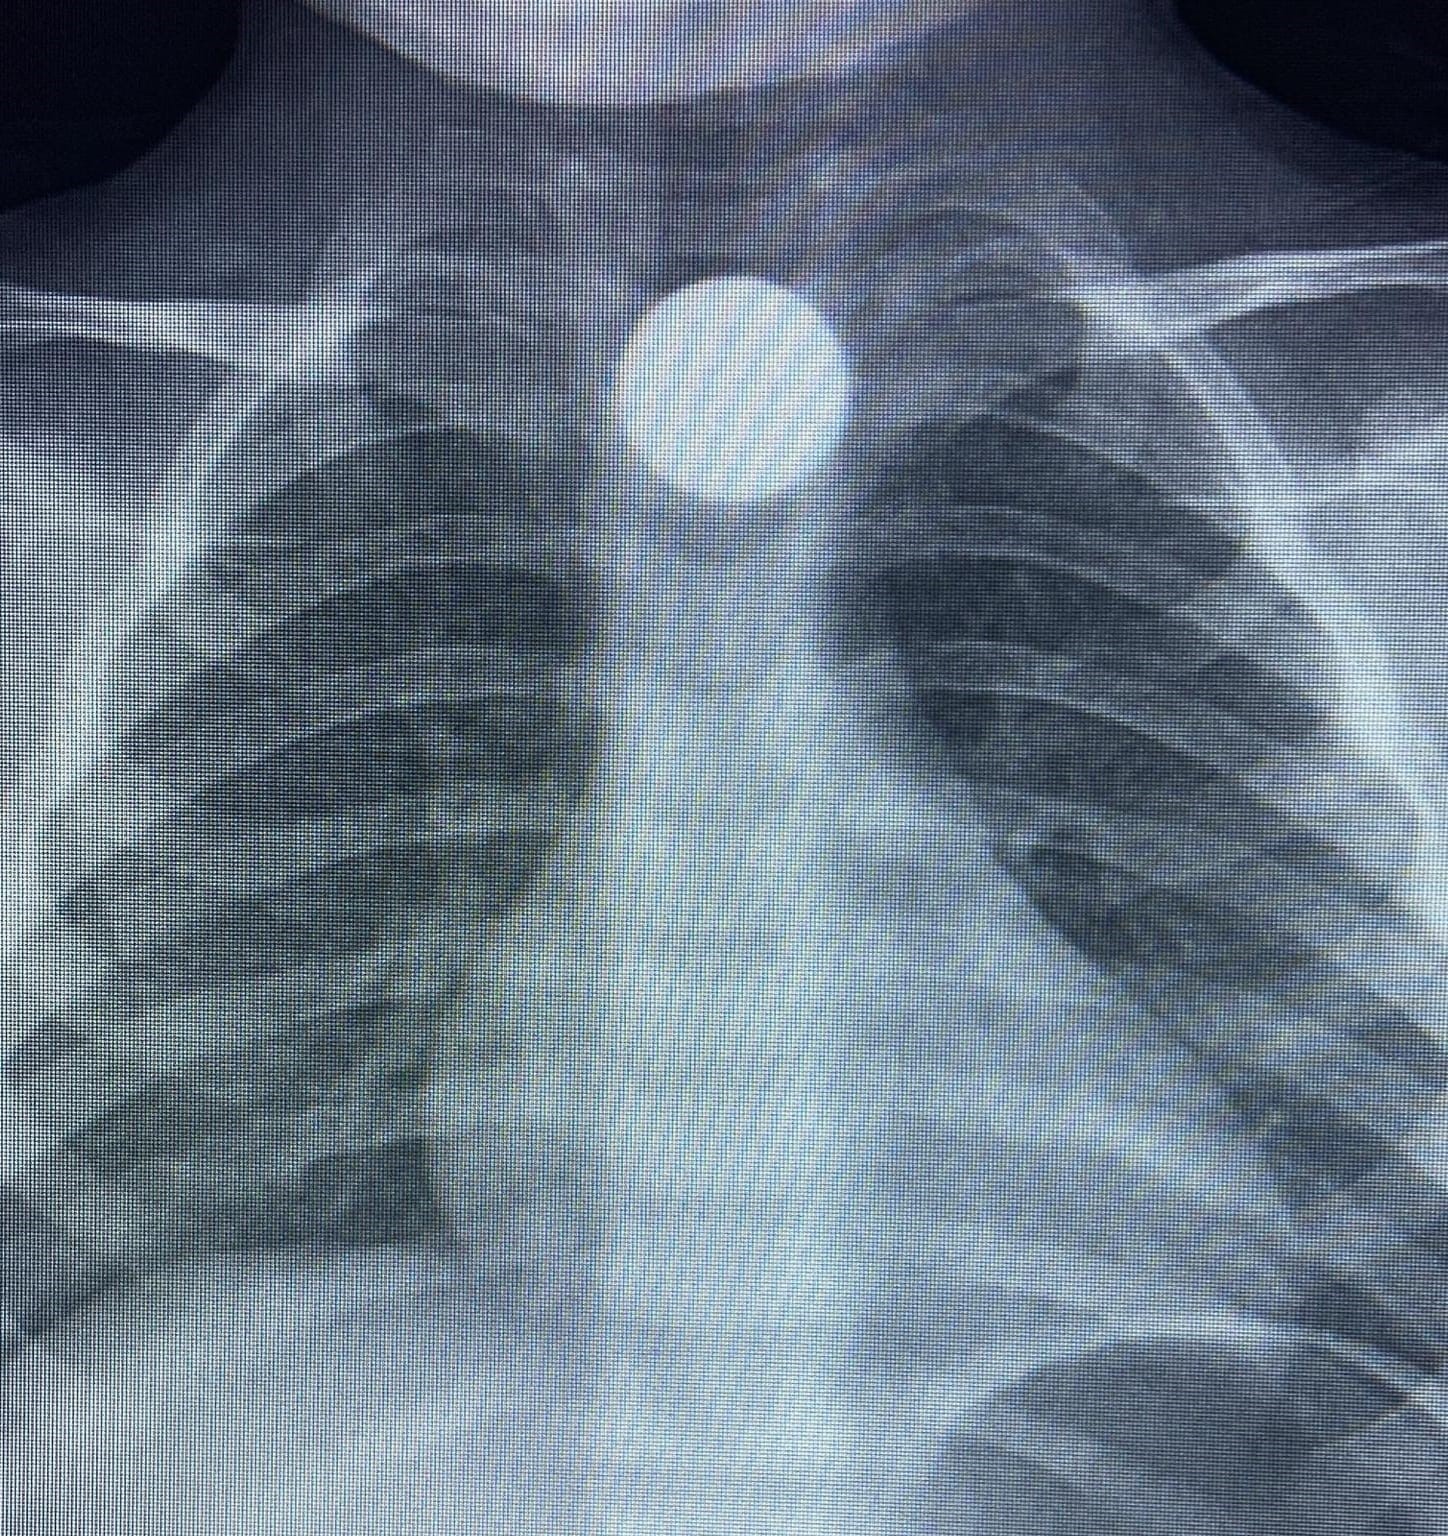

Olay, İnegöl’ün kırsal Yeniceköy Mahallesi’ndeki bir evde meydana geldi. 3 yaşındaki Bilal K., evde yerde bulduğu 50 kuruş madeni parayı ağzına atıp yuttu. Olayı fark eden ailesi tarafından çocuk özel araçla İnegöl Devlet Hastanesi’ne kaldırıldı. Yapılan tetkiklerde yemek borusunda takılı kalan madeni para görüldü. Çocuk ilk tedavinin ardından ambulansla Bursa...

Olay, İnegöl’ün kırsal Yeniceköy Mahallesi’ndeki bir evde meydana geldi. 3 yaşındaki Bilal K., evde yerde bulduğu 50 kuruş madeni parayı ağzına atıp yuttu. Olayı fark eden ailesi tarafından çocuk özel araçla İnegöl Devlet Hastanesi’ne kaldırıldı. Yapılan tetkiklerde yemek borusunda takılı kalan madeni para görüldü. Çocuk ilk tedavinin ardından ambulansla Bursa Yüksek İhtisas Eğitim Ve Araştırma Hastanesi’ne sevk edildi.